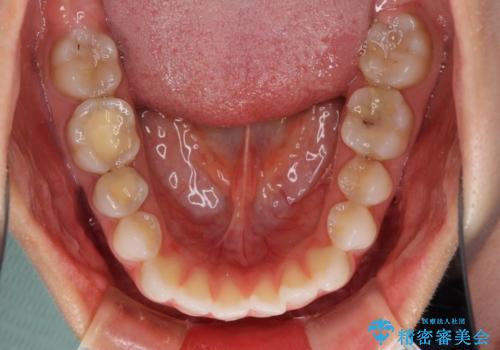

- 上下の前歯の反対咬合を気にして来院された患者様です。

インビザラインを用い、下顎はIPR(歯と歯の間を削る)と歯列全体を後方に移動させ、上顎は前歯を持ち上げることで、反対咬合を改善していくこととしました。

インビザラインによる反対咬合の改善は、上の歯が下の歯を乗り越えていく期間に咬み合わせが非常に不安定となり、治療が長期化することがあります。

こちらの患者様も、一時的に前歯でしか咬めない時期がありましたが、比較的早く咬み合わせが安定し、1年ほどで治療を終えることができました。